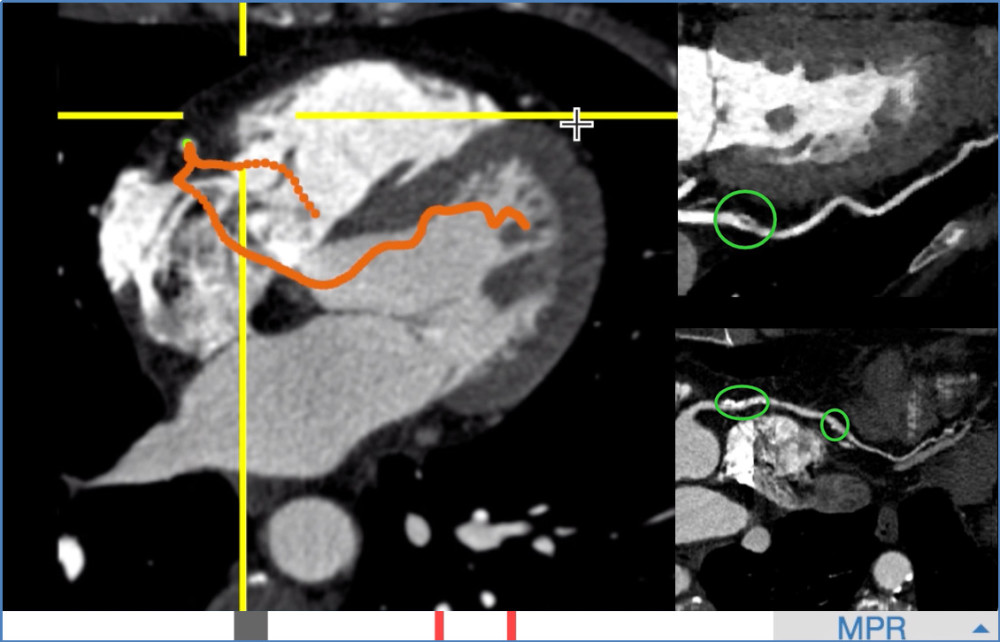

阿里AI在0.5秒内全自动提取的单根心脏冠脉,医生可从重建的影像上快速发现病灶。右上为血管上的软斑块,右下为钙化斑块。

传统的心脏冠脉中心线提取方法大多存在人工交互多、耗时长等缺点。阿里巴巴提出了判别式冠脉追踪模型。这一模型由三维卷积神经网络构成,充分利用三维空间特征,可从影像中迭代搜索完整血管,且正确区分冠脉与静脉。

在学习了数十万个训练样本后,阿里AI无需人工交互,仅用0.5秒就能提取单根冠脉血管,提取完整冠脉树用时不超过20秒,相比传统方法效率提升近百倍。传统算法需要处理整个影像,阿里AI则能自动忽略冗余信息,大大提高效率。